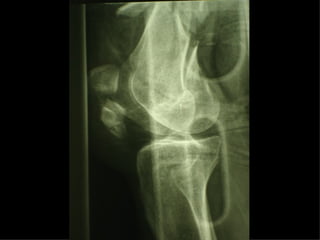

F. 75a